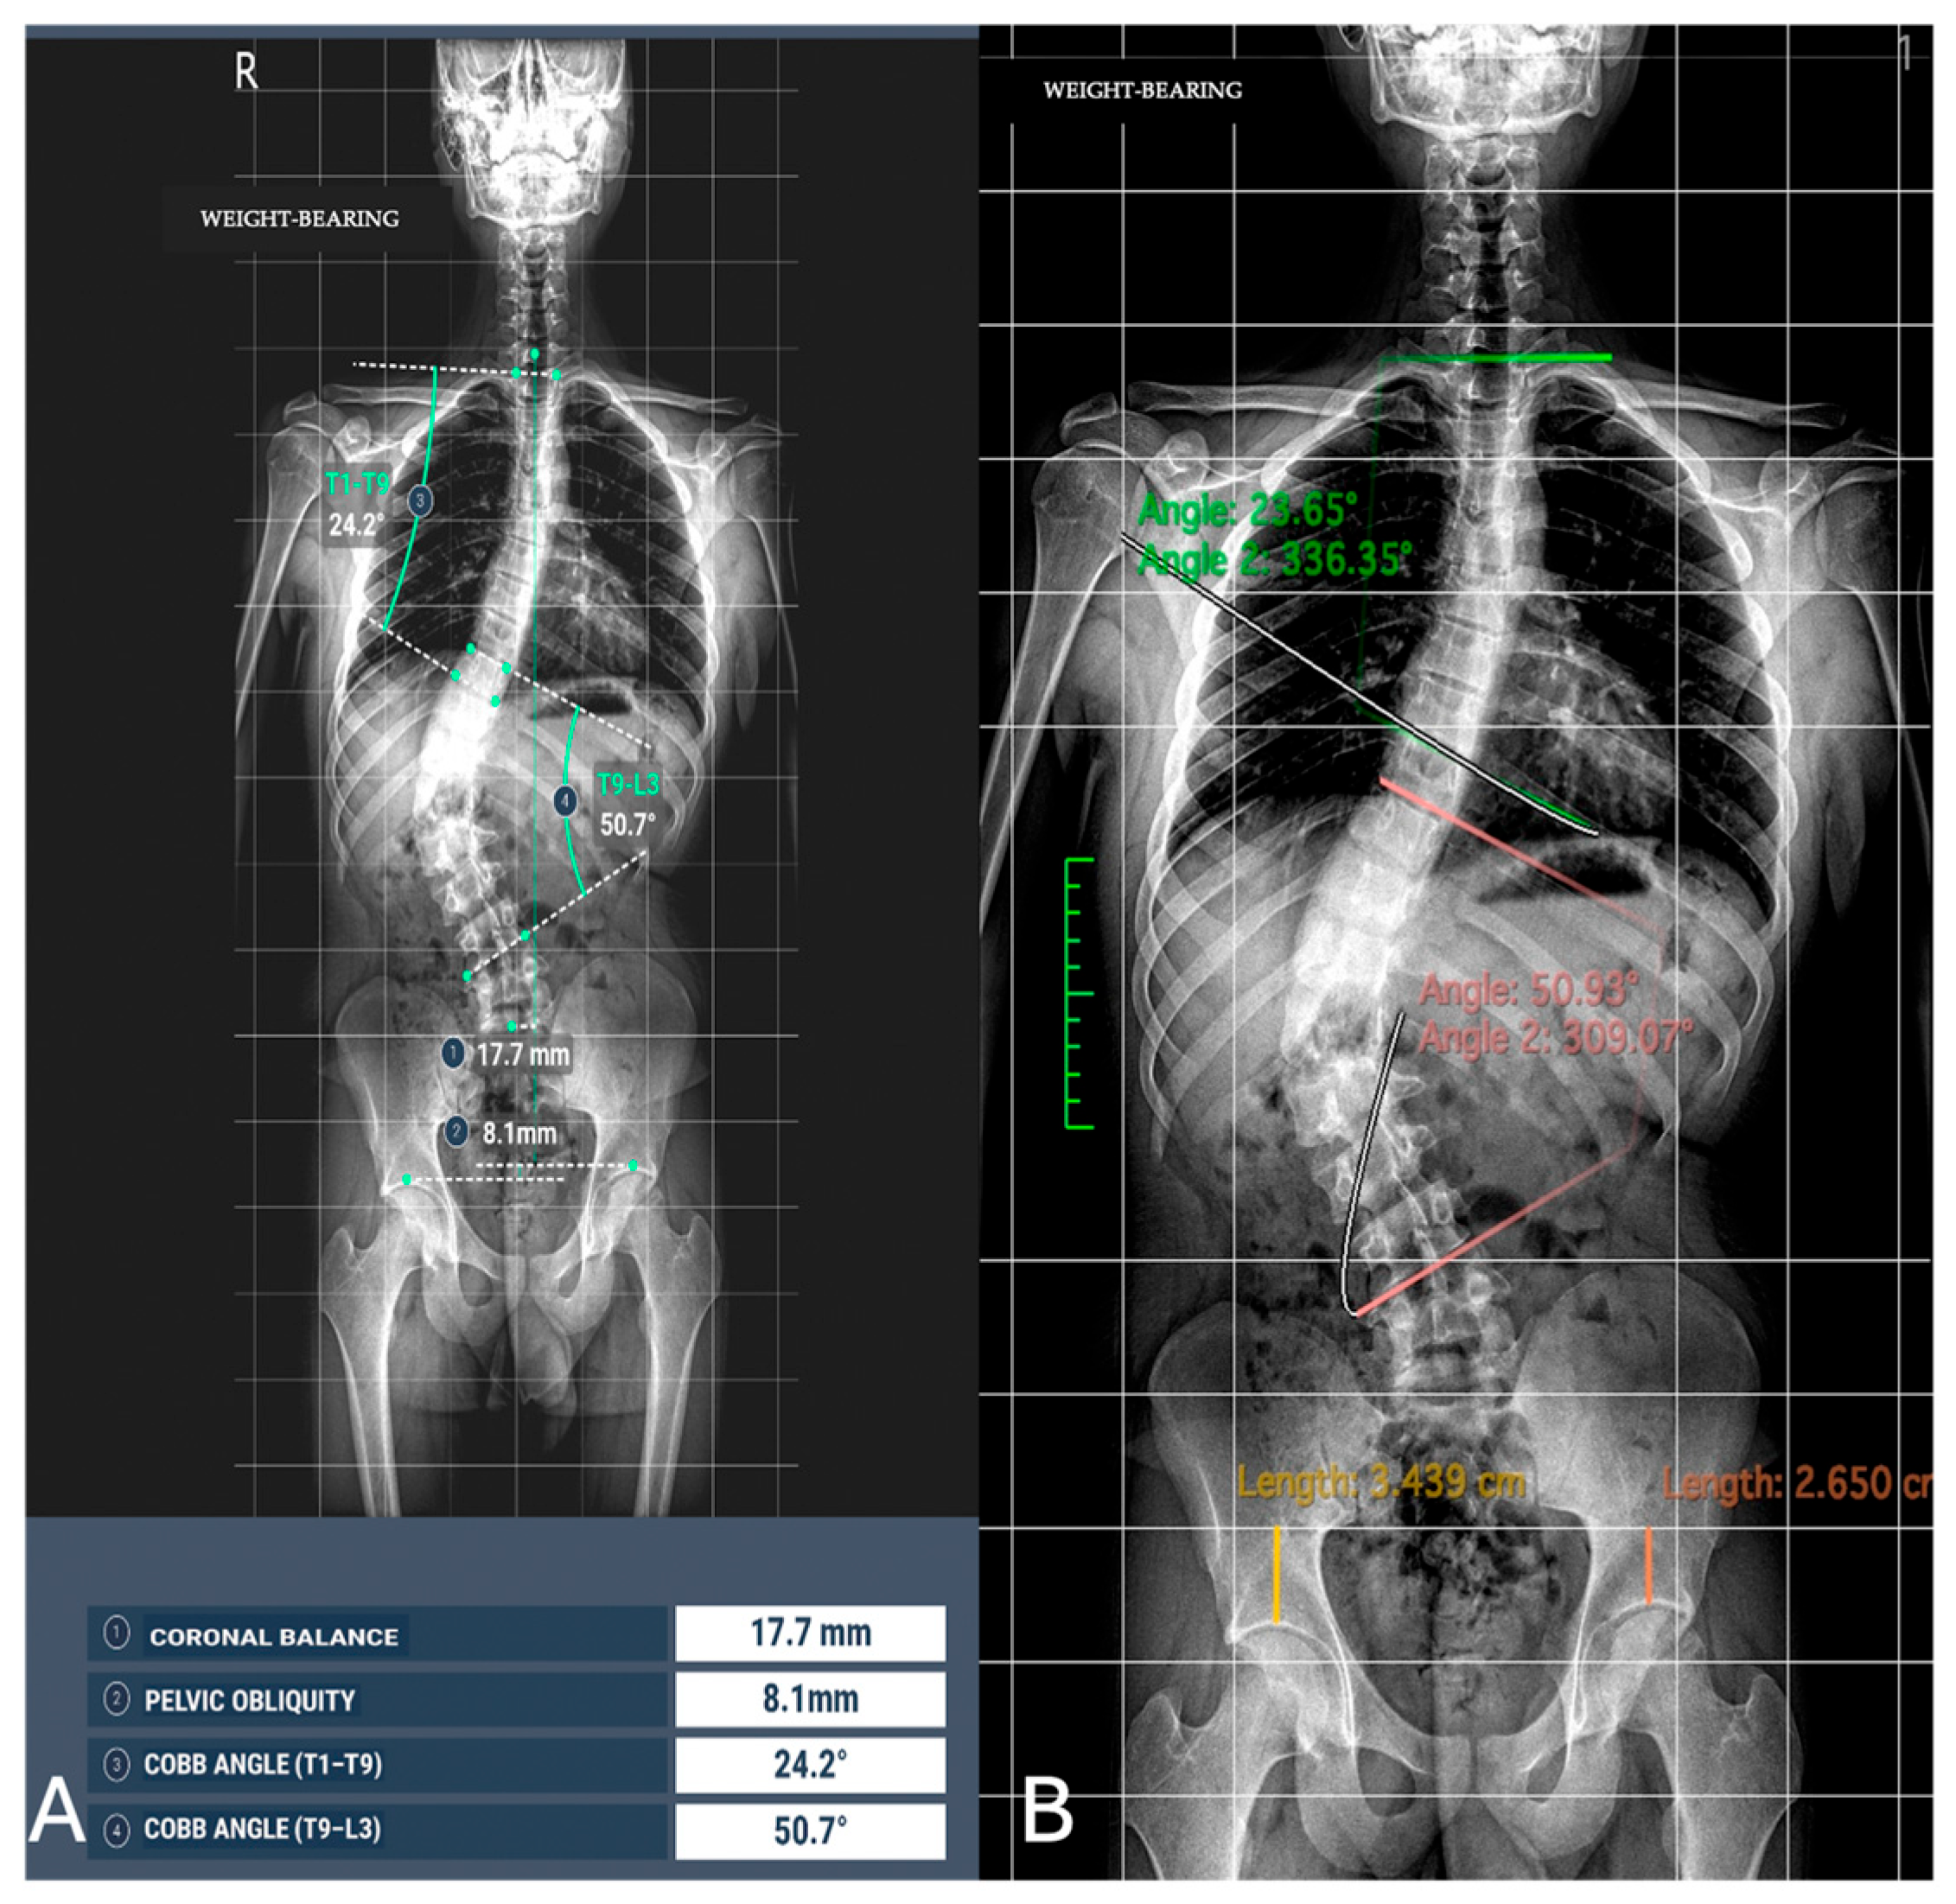

All images were acquired using the same digital radiography scanner (Bloomix 120 ED-R, Trade Art Manifacturing, Via della Pisana 1353, 00163 Rome, Italy) with patients in a standing weight-bearing position, in order to reproduce physiological load conditions on the spine. For each patient, both anteroposterior (AP) and lateral projections were obtained, covering the entire spine from the second cervical vertebra (C2) to the last sacral vertebral body (S5), including the pelvic bones and both femoral heads to allow evaluation of spinopelvic parameters. The dedicated scanner used in this study enables the acquisition of the entire spine in a single exposure, without the need for image stitching, thus reducing potential misalignment artifacts and ensuring greater measurement accuracy. Standardized positioning protocols were adopted to minimize patient rotation and to maintain consistent image quality across all examinations. All acquisitions were performed by experienced radiographers according to the department’s routine protocol for whole-spine evaluation. Exposure parameters, such as tube voltage and current, were adjusted based on patient size and age to optimize image quality while maintaining the radiation dose as low as reasonably achievable (ALARA principle) (Figure 1).

Figure 1. Full-spine radiographs were acquired in standing position using the same dedicated scanner (Bloomix 120 ED-R). (A) Anteroposterior (AP) view; (B) lateral view. For each patient, AP and lateral projections were obtained from the base of the skull to the last sacral segment, including the hip bones and femoral heads. The scanner enabled the acquisition of the entire spine in a single shot, without the need for image stitching.

Figure 3. Image analysis of Cobb angle and pelvic obliquity in the same patients. (A) Automated measurements; (B) radiologist measurements.